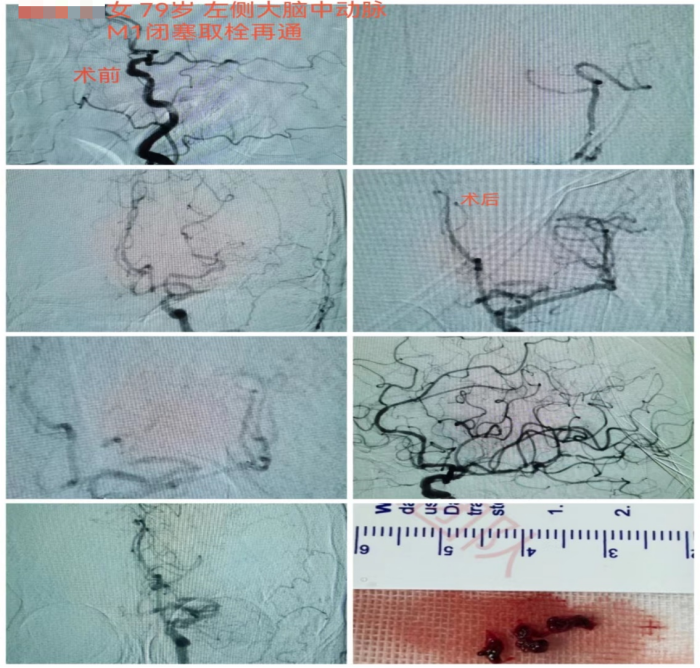

8月19日上午6时左右,家住天心区79岁的蒋奶奶因四肢乏力在客厅摔倒,家属扶起后症状未见好转,且无法言语。

9时左右,家属将蒋奶奶送至长沙市融城医院,行头部CT和MRI后考虑左侧大脑中动脉闭塞引起的脑梗死,需立即接受动脉取栓治疗。长沙市融城医院立即联动香港马会app

12时24分,“120”救护车到达香港马会app

)急诊,立即完善头颅CTA提示左侧大脑中动脉M1段栓塞。监测生命体征以及复查必要检查项目后,神经内科副主任医师冯铁桥与患者家属沟通病情及手术相关事项,签字后患者被转入早已做好准备的介入导管室,行“左侧大脑中动脉闭塞急诊介入开通术”,施行动脉取栓。

12时45分,患者被推进介入导管室,此时患者仍处于颅内大血管闭塞动脉取栓的黄金时间窗内(6小时),救治工作紧张有序地展开。10分钟后股动脉穿刺成功,患者的取栓血管通路顺利建立。

13时33分,患者闭塞的血管被开通,缺血的脑组织恢复有效的血流灌注。术后,患者血管再通良好,闭塞远端血流较前明显改善。患者右侧肢体肌力明显较发病时好转,能简单发声、听懂对话。

第二天,患者能自行下地行走,语言功能也得到恢复。从卒中发病到完成介入取栓治疗,蒋奶奶的“生死时速”过程历经6小时40分钟。